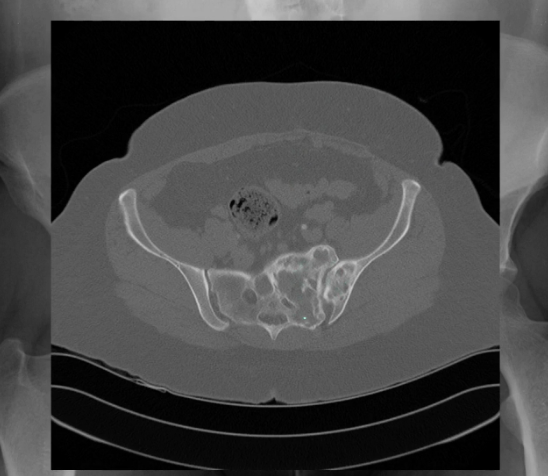

polyostotic Fibrous dysplasia